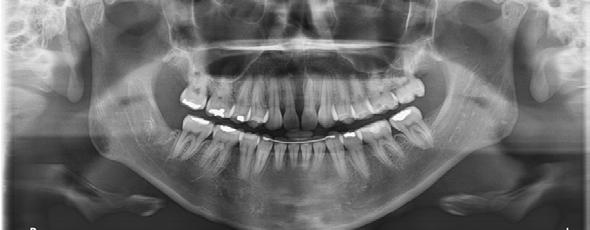

En la ortopantomografía se observó asimetría de las ramas mandibulares, reabsorción radicular severa del diente 21, extrusión de incisivos inferiores y presencia de los dientes 18, 28 y 48 (Figura 2 A). La radiografía lateral de cráneo nos permitió realizar el análisis cefalométrico de Ricketts en el cual se confirmó la clase II esqueletal, el biotipo dolicofacial y la retrusión mandibular (Figura 2 B y C y Tabla 1).

Figura 2. Radiografía ortopantomografía y lateral de cráneo.

En la ortopantomografía se puede apreciar el cierre de la mordida abierta anterior y la preservación de las longitudes radiculares en general (Figura 7A). En la radiografía lateral de cráneo y superposición final se puede observar la mejora general del perfil de la paciente y de sus inclinaciones dentales (Figura 7 B-D) (Tabla 1).